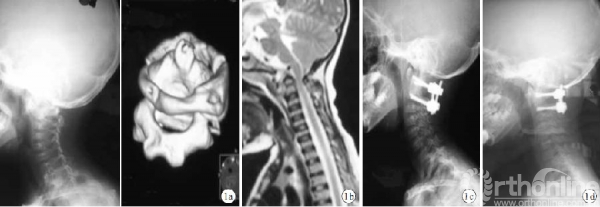

本组手术均顺利完成。手术时间75~135min,平均89min;术中出血量50~400mL,平均95mL;术后引流量60~100mL,平均73mL;住院时间10~45d,平均14d。19例均获随访,随访时间6~27个月,平均18.3个月。X线片、CT复查示寰枢椎均获满意融合;植骨均融合,融合时间3~7个月,平均4.5个月。随访期间无断钉、断棒以及寰枢椎再脱位发生(图1、2)。1例患儿术前ASIA分级为C级,术后2年因齿状突生长致颈髓角增加,再次出现瘫痪症状,取出内固定物后脊髓损伤进一步加重,经保守治疗症状缓解不明显,转至上级医院治疗后失访;余18例随访期间枕颈部未出现畸形。患儿枕颈部疼痛、活动受限及瘫痪等临床症状均明显缓解。

儿童寰枢椎解剖结构及椎骨大小与成人不同,且寰椎后弓表面缺少明显的进钉点解剖标志,故儿童寰枢椎行椎弓根螺钉系统固定有一定难度。Resnick等应用CT对寰枢椎进行测量,结果示儿童寰椎椎弓根平均宽度约7.9mm,可容纳直径3.5mm的椎弓根螺钉。马向阳等和谭明生等对寰枢椎进钉点位置和寰枢椎植钉可行性进行研究,为寰枢椎椎弓根螺钉治疗寰枢区不稳提供了解剖学基础。随着现代影像技术的发展,术前能够清楚显示患儿骨骼结构及不稳定状况,并从不同角度和方向显示椎弓根钉道,从而制定个体化手术方案,提高手术成功率。术前我们通过对患儿上颈椎进行CT三维重建、寰枢椎椎弓根钉道设计,仔细评估椎弓根大小及椎弓根螺钉的可行性,结果显示患儿椎弓根适合椎弓根螺钉的植入,并取得良好疗效。